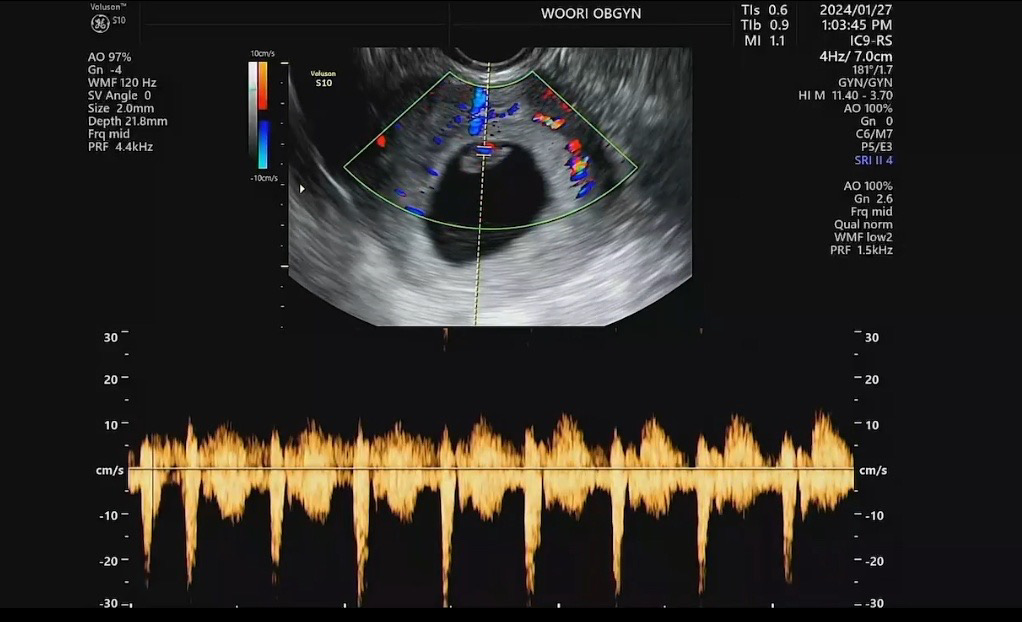

늦은 착상에 걱정했는데 심장소리 듣고 왔어요🥹

막생 11.27 두 줄 처음 확인 12.30 한 주 늦게 착상이 되어서 네이버 주수 대비 1주일 늦었는데 5주 초반에 가서 아기집 커진 것만 보고 난황이나 아가를 못 봐서 지난 2주 간 엄청 마음 졸였었어요ㅠㅠ 오늘 가서 배 초음파로 안 보여서 충격이었는데 질 초음파 하니 아기 0.99cm에 난황도 잘 있고 심장소리도 쿵쾅쿵쾅 잘 뛰어서 눈물이..😢 임신증상도 별로 없고 단축근무는 커녕 연초부터 매일 열시까지 야근하고 그랬는데 컨디션 자체는 괜찮았거든요. 그래도 아무튼 심장소리를 못 들어서 걱정 태산이었는데 이제 한시름 놓여요ㅠㅠ.. 걱정하시는 분들 맘 편하게 드시고 병원 다녀오시길 바래요 아가 잘 크고 있을 거에요!!

밑에 황금색 심장파동이 넘 좋으네요!!!